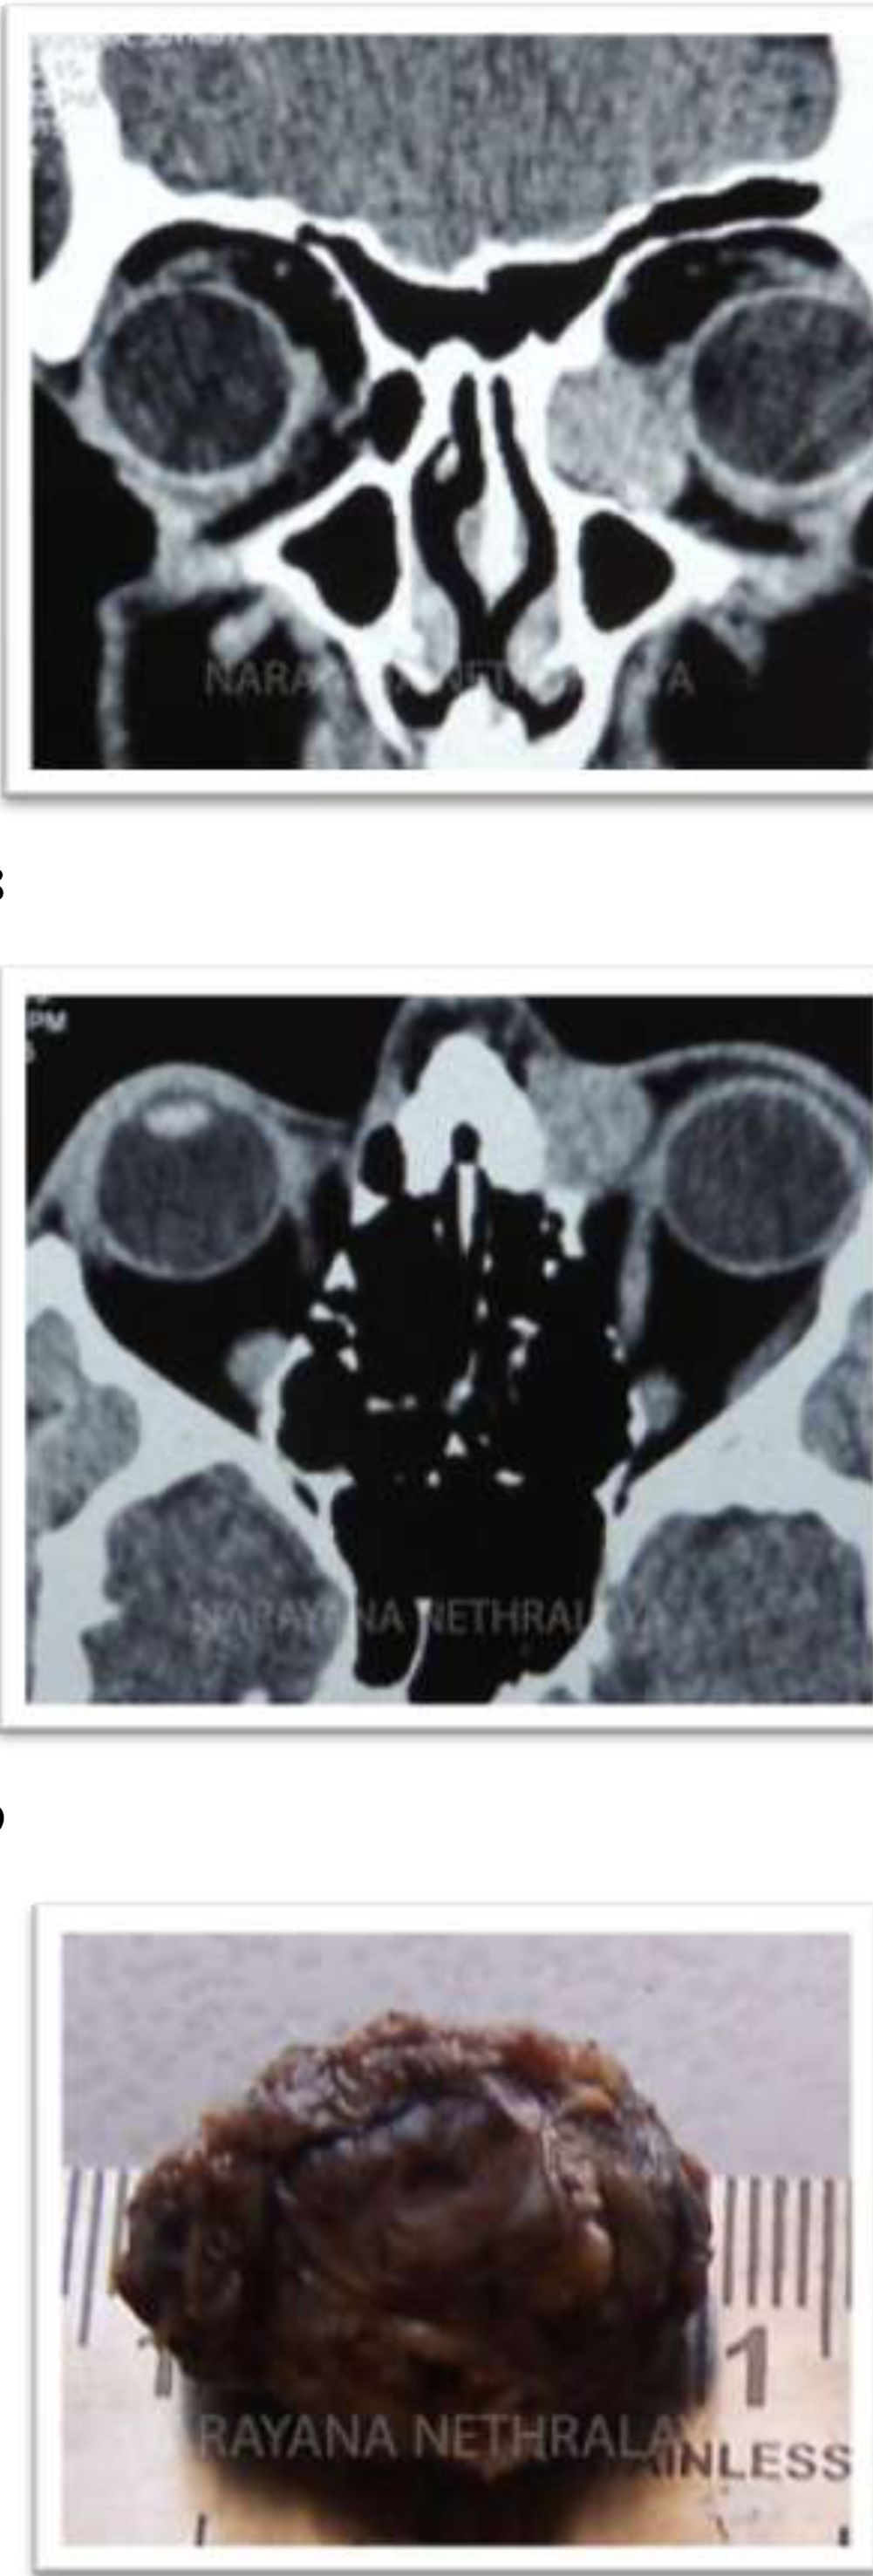

Figure 8,9:

Computerized tomography of orbit shows homogenous mass from sac area, extending into extraconal medial orbit scalloping the bone. Coronal and axial sections respectively.

Figure 10:

Histopathology shows excised well circumscribed mass, removed in toto.

Figure 11,12:

Histopathology : Photomicrograph showing tumor cells arranged in lobular pattern with intervening fibrovascular septa.